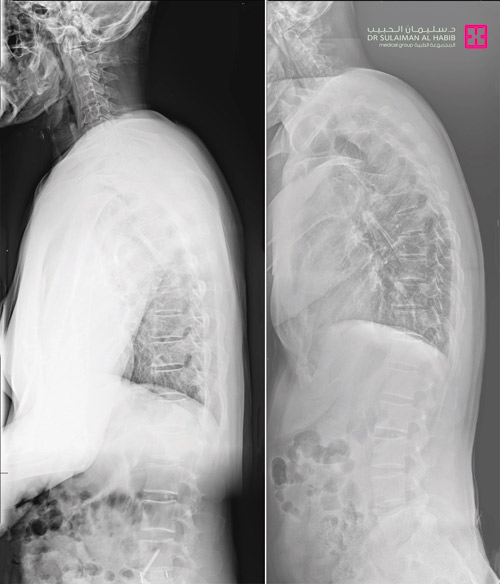

وأضاف د. السفياني أنه أجريت للمريض الفحوصات والأشعة اللازمة وقد تأكد وجود تآكل بالغضروف بين الفقرة الرابعة والخامسة والفقرة الخامسة والعجزية الأولى، مع فقدان الانحناء الطبيعي للفقرات القطنية. وقد ناقش الفريق الطبي الحالة، مع وضع الحالة الصحية العامة للمريض في الاعتبار.

وتبين أن الدخول الجراحي عن طريق الظهر ينطوي على احتمالات عدم التئام الفقرات، خاصة أن المريض مدخن ويستهلك علبتين يومياً، وقد استقر رأي الفريق على الدخول من البطن من خلف الجدار البطني,

وقد أجرى الفريق للمريض عملية معقدة، بمساعدة د ناصر الوهيبي استشاري جراحة الأوعية الدموية لتأمين سلامة الشرايين الرئيسية بالبطن، وتم تبديل الغضروفين، وفتح القناة العصبية بالكامل من الأمام، وقص عظمة من الحوض لاستخدامها «ترقيع عظمي» لزيادة التئام ودمج الفقرات. ومضت العملية بسلاسة وانتهت ولله الحمد بالنجاح التام، ونقل المريض إلى غرفة التنويم، حيث أمضى فيها «5» أيام، تحسنت خلالها حالته، وأستعاد قدرته على المشي بعد نحو «24» ساعة. وأكدت صور الأشعة بعد يوم من العملية تحسن استقامة الظهر بشكل كبير. وغادر المريض المستشفى بحالة صحية ونفسية ممتازة، وقد تخلص من معظم الأعراض وتراجعت حدة المتبقي منها، وتحرر من قيود ضعف الحركة، وعاد لممارسة حياته بصورة طبيعية.